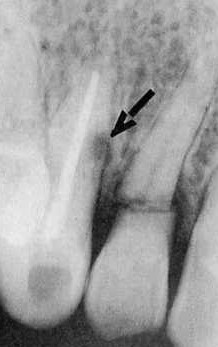

U pacjenta w wypadku komunikacyjnym doszło do urazu zębów 12 i 13. Ząb 13 uległ całkowitemu zwichnięciu, a w zębie 12 stwierdzono złamanie korzenia w przykoronkowej części. Ząb 13 replantowano po przeprowadzonym leczeniu endodontycznym, a pacjent regularnie zgłaszał się na wizyty kontrolne. Po 34 miesiącach od replantacji zęba 13 wykonano kontrolne zdjęcie rentgenowskie (ryc. 1). Odpowiedz, co wskazuje strzałka na rycinie: